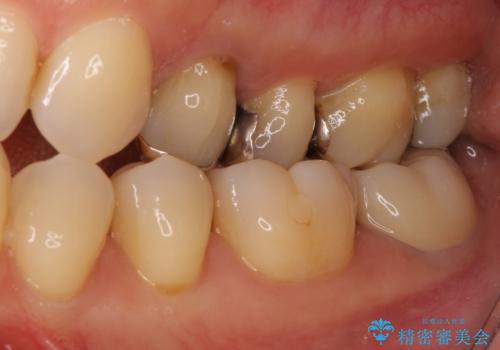

- 神経が取り除かれた歯が欠けてしまったとのことで来院された患者様です。

破折線が歯肉の中、深いところにまで及んでいる場合には歯周外科の適用となることを伝えた上で、補綴治療を行うこととしました。

破折部位を除去したところ、外科処置が必要な深さまで破折線が及んでいなかったため、速やかにジルコニアクラウンにて補綴を行うことになりました。

神経が取り除かれた歯、特に奥歯では、歯の破折が起こりやすいので、クラウンによる補綴治療が必要であることを実感した治療でした。